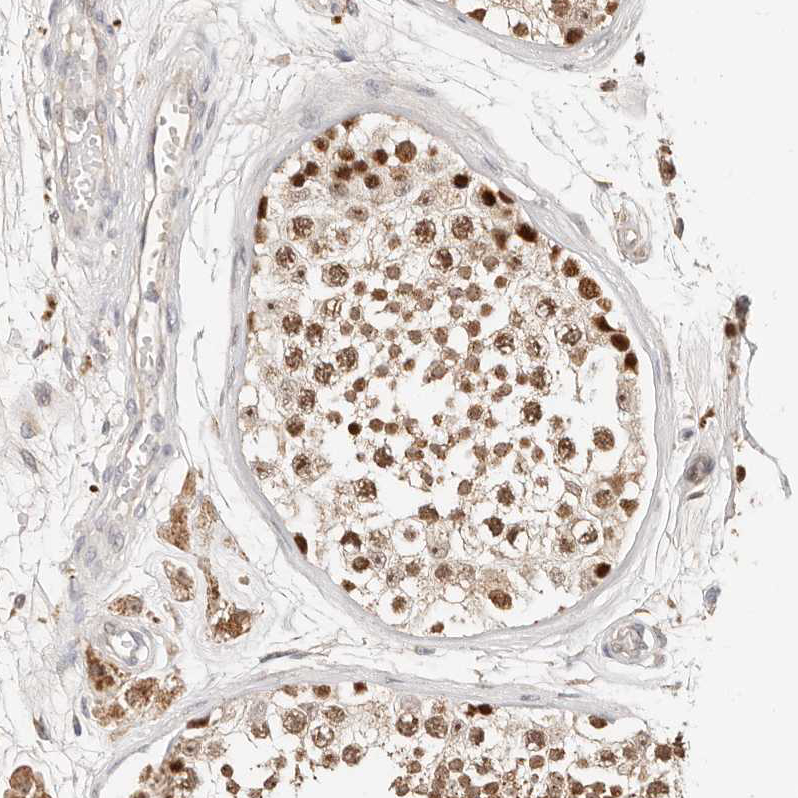

Immunohistochemical staining of human testis shows strong nuclear positivity in cells in seminiferous ducts.